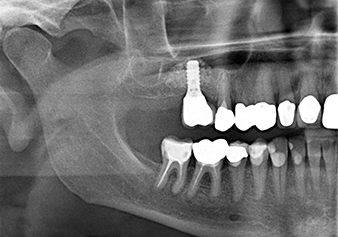

La radio de contrôle montre une structure de tissu dur péri-implantaire bien homogène.

Fig.10 : Six bons mois plus tard, après la pose de la couronne définitive, la radio de contrôle montre une structure de tissu dur péri-implantaire bien homogène.